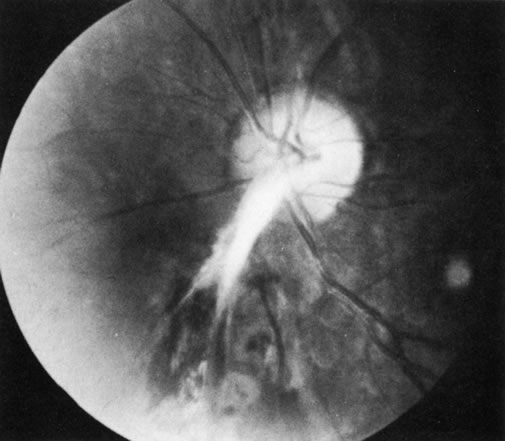

The Vogt-Koyanagi-Harada syndrome (VKHS) is a chronic, bilateral, exudative uveitis associated with whitening of the hair and eyelashes (Fig. 8), vitiligo, and meningeal irritation. It is a combination of two overlapping disease entities. VKHS is a severe anterior-segment inflammation associated with dysacousia, vitiligo, alopecia, and poliosis. Harada's disease is limited largely to posterior uveal inflammation with serous retinal detachments, disc involvement, meningeal inflammation, and sometimes skin and hair changes (Figs. 9 and 10). Because the symptoms of the two diseases overlap significantly and their histopathologic features are similar, the two are now regarded as a single disease entity.

Fig. 9. Optic nerve involvement in Vogt-Koyanagi-Harada syndrome. (Courtesy of Dr. R. Weinberg.)

Fig. 10. Posterior involvement in Vogt-Koyanagi-Harada syndrome with pigmentary changes and scarring. (Courtesy of Dr. R. Weinberg.)